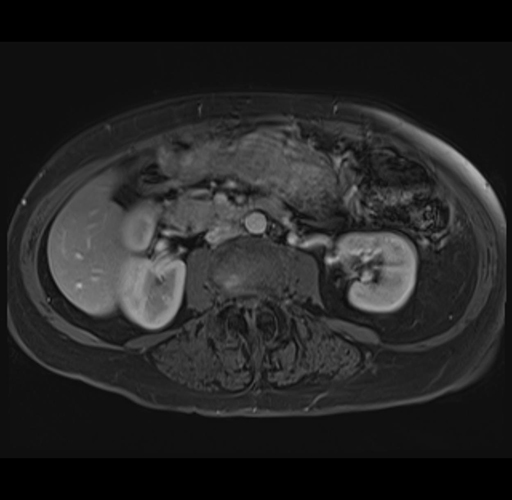

Axial Venous

MRI T1